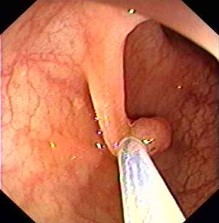

Darmpolypentfernung / ambulante Polypektomien

Gummibandligaturbehandlung (Barron Ligatur)